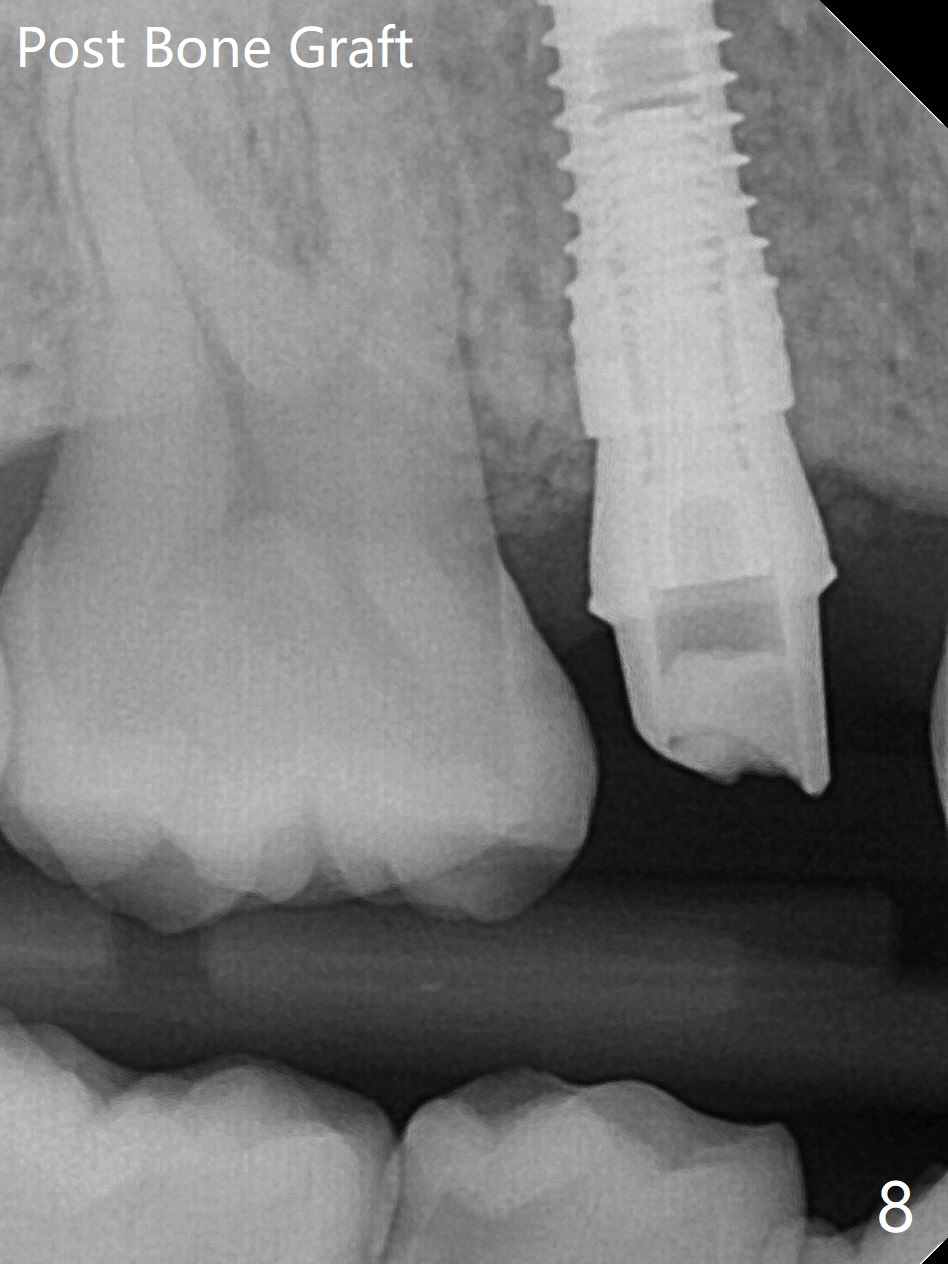

4号牙残根(图一)无创伤拔除使用一种叫做proximators牙周刀(periotomes,图二,三)。初期钻洞方位尚可(图四,五),植入3.8x15毫米植体,扭力50Ncm,修复成品基台完全就位(图六,七),植体,基台周围间隙填入骨粉(用血液调袢)后,制备基台(图八)和临时牙冠。